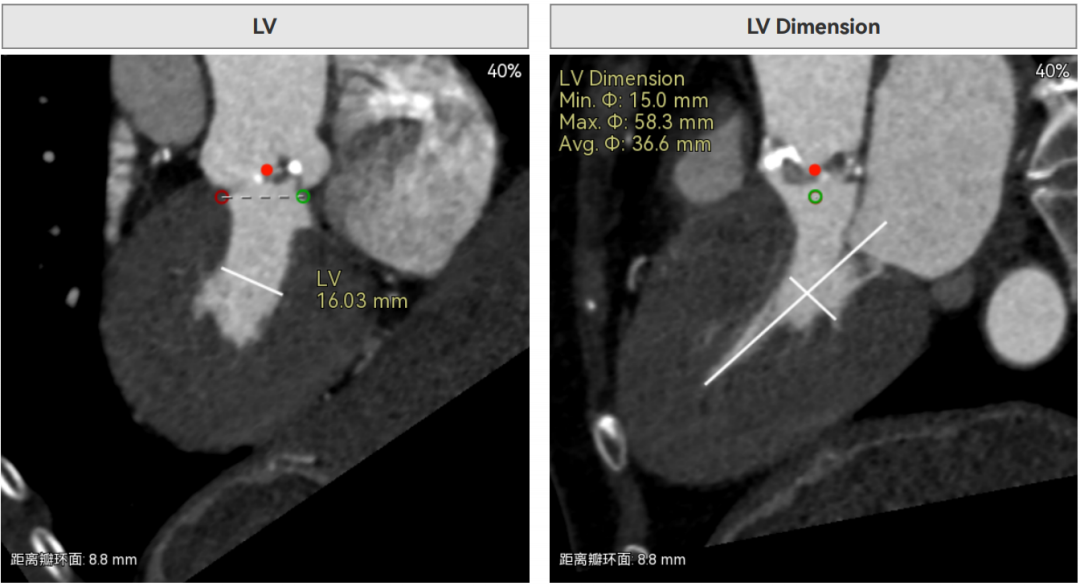

主动脉瓣环周长径18.4mm,极小瓣环,LVOT直筒型结构;Type0型二叶瓣,鱼嘴处最窄预估宽度16.9mm。心脏角度34°,窦部空间大,无冠脉风险。

HU850钙化积分644,中重度钙化,瓣上限制较重,对瓣膜径向支撑力有一定要求,自杀左室,术前合并轻度反流,有一定循环崩溃风险。

4.自杀左室:术前超声关键指标显示,患者左心室收缩末期内径仅 16mm,属于典型 “自杀左室”—— 左室腔极度狭小,意味着心脏循环储备功能已濒临临界状态。这一解剖特点带来致命性挑战:一是手术耐受性极差,球囊预扩张、瓣膜植入等操作过程中,任何短暂的血流阻断或心肌牵拉都可能诱发血压骤降、恶性心律失常,甚至直接导致低心排血量综合征或循环崩溃;二是与极小瓣环叠加后,血流动力学调节难度呈指数级上升,需在解除瓣口狭窄的同时,避免加重左室负荷,否则可能引发急性心衰,三是左室腔狭小导致瓣膜锚定空间不足,若瓣膜扩张后与左室流出道不匹配,可能加剧梗阻风险,进一步恶化循环功能。